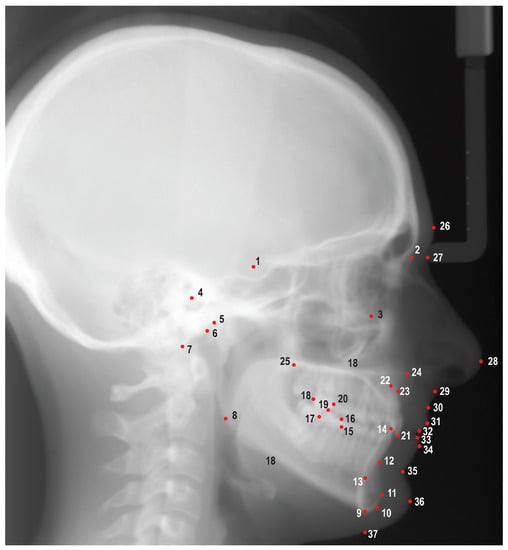

Digital images from the AAOF repository were uploaded into Dolphin Imaging v. 11.95 (Dolphin Imaging and Management Solutions, Chatsworth, CA, USA) and were traced by a single investigator (M.P.) using 25 hard tissue landmarks and 12 soft tissue landmarks (Figure 1). A total of 47 linear and angular measurements were measured and recorded; definitions of the measurements are listed in Table S1. Images were scaled by using fiducial data embedded on the images as described in reference material provided by the AAOF. Fiduciaries are reference marks located on the images with known coordinate values allowing the user to compute the scale of the image. The demographic and cephalometric data were subsequently entered into a spreadsheet and securely stored in a cloud service (OneDrive, Microsoft Co., Redmond, WA, USA). To evaluate the repeatability of measurements, a research randomizer was employed to randomly choose 10 images for retracing. The ICCs were utilized to assess the repeatability of these measurements.

Figure 1. Cephalometric landmarks used in this study. 1. Sella (S), 2. Nasion (N), 3. Orbitale (Or), 4. Porion (Po), 5. Condylion (Co), 6. Articulare (Ar), 7. Basion (Ba), 8. Gonion (Go), 9. Menton (Me), 10. Gnathion (Gn), 11. Pogonion (Pog), 12. B point (B), 13. Lower incisor root apex (L1a), 14. Lower incisor incisal edge (L1i), 15. Mesial of lower first molar (L6m), 16. Mesiobuccal cusp of lower first molar (L6mb), 17. Distal of lower first molar (L6d), 18. Distal of upper first molar (U6d), 19. Mesiobuccal cusp of upper first molar (U6mb), 20. Mesial of upper first molar (U6m), 21. Upper incisor incisal edge (U1i), 22. Upper incisor root apex (U1a), 23. A point (A), 24. Anterior nasal spine (ANS), 25. Posterior nasal spine (PNS), 26. Glabella (G), 27. Soft tissue nasion (N′), 28. Pronasale (Pn), 29. Subnasale (Sn), 30. Soft tissue A point (A’), 31. Upper lip (Ls), 32. Stomion superioris (Ss), 33. Stomion inferioris (Si), 34. Lower lip (Li), 35. Soft tissue B point (B’), 36. Soft tissue pogonion (Pog′), 37. Soft tissue menton (Me′).